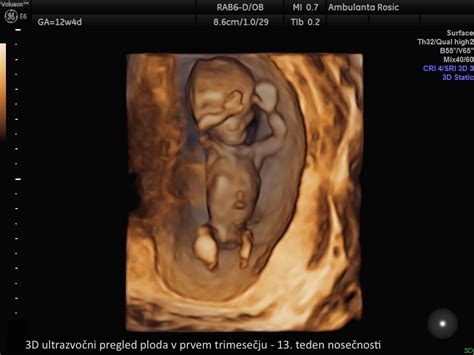

V prvih treh mesecih nosečnosti se telo nosečnice začne prilagajati na novo stanje. Pojavljajo se lahko jutranje slabosti, povečana občutljivost prsi in pogostejše uriniranje. Kljub temu, da zunanje spremembe niso očitne, se v telesu dogajajo pomembni procesi: srce zarodka začne utripati že okoli 6. tedna, razvijajo se osnovni organi, kot so jetra, pljuča in ledvice, čeprav bodo ti še dolgo časa dozorevali. Do konca prvega trimesečja (12. teden) je plod že dobro oblikovan, z izoblikovanimi okončinami, prstki na rokah in nogah ter že začetnim razvojem čutil. V tem obdobju je mogoče opraviti tudi genetske preiskave, kot je merjenje nuhalne svetline, ki lahko pomagajo oceniti tveganje za kromosomske nepravilnosti.